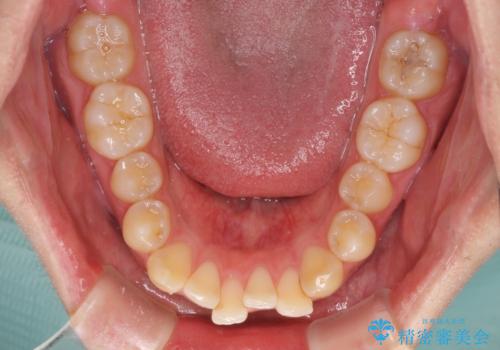

前歯のデコボコと突出感 インビザラインにて矯正治療

- 上下前歯のデコボコを気にして来院された患者様です。

インビザラインによる上下歯列の側方拡大と後方移動、IPR(歯と歯の間を削る)にるスペースの獲得により歯列を整えることとしました。

左上の小臼歯は捻転が強く、あえて180逆向きの状態で終了させる治療計画としました。